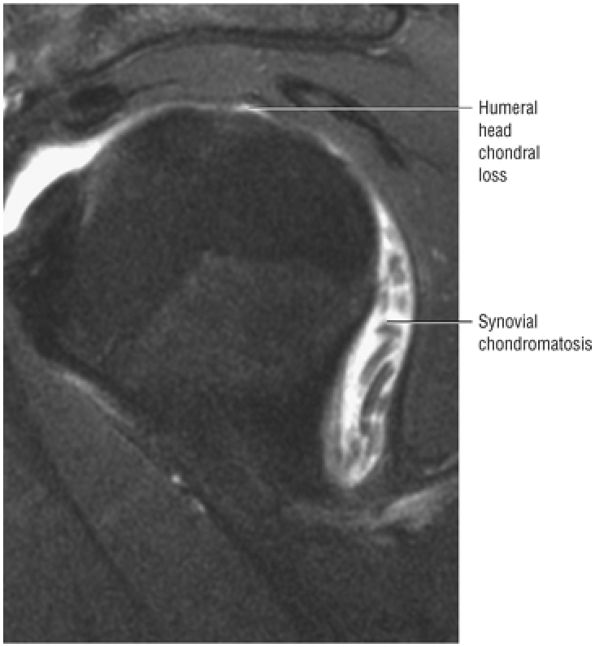

-

Subacromial keel spurs are located on the anteroinferior lateral portion of the acromion.

Acromial thickness is important in planning subacromial decompression procedures.